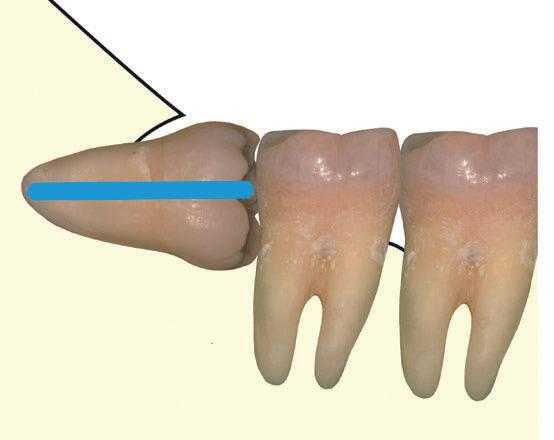

Questo schema illustra la quantità di dente rimosso (sezionamento della corona), l’angolo di accesso e la direzione dell’estrazione del dente. Fig. 139

Il blu indica la quantità di dente rimosso quando esso viene sezionato orizzontalmente, mentre il rosso quando è sezionato verticalmente.

Fig. 139 - Questo schema illustra la quantità di dente rimosso (sezionamento della corona), l'angolo di accesso e la direzione dell'estrazione del dente.